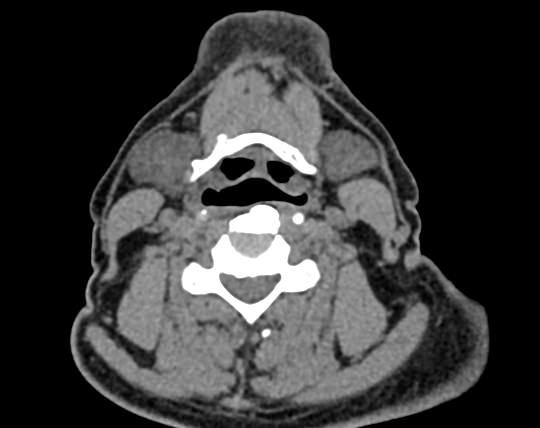

Используемые в нашей клинике томографы, благодаря своему оснащению, позволяют получать снимки высокого качества и детализации за короткий промежуток времени, что минимизирует уровень лучевой нагрузки на организм. Используя полученные данные, аппараты создают трехмерные реконструкции анатомической зоны. Это дает возможность наглядно оценить пространственное соотношение лимфатических узлов и близлежащих органов, выявить прорастание в окружающие ткани, особенно при образовании цепочек, пакетов и конгломератов лимфоузлов.

Для повышения качества визуализации лимфоузлов, особенно при подозрении на онкологических процесс, исследование проводится с внутривенным болюсным контрастированием. Контрастный препарат, содержащий йод, вводится в вену с помощью автоматического шприца. Распространяясь по сосудистой системе, препарат накапливается в патологических очагах, в том числе, в измененных лимфоузлах, и увеличивает их яркость на КТ-изображениях. Методика контрастирования помогает выявлять опухоли минимальных размеров, проводить дифференциальную диагностику между доброкачественными и злокачественными новообразованиями и воспалительными изменениями.

Мультиспиральная КТ позволяет оценить размеры лимфатических узлов, выявить деформацию их контуров, неоднородность структуры, установить точную локализацию, взаимодействие с близлежащими органами и окружающими тканями, обнаружить инфильтрацию прилегающих структур.